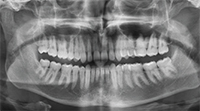

Deep Bite

A Townie wonders how to treat a patient with a deep bite who is dissatisfied with his profile.